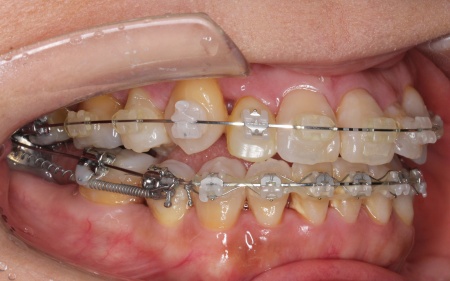

治療中

ワイヤー矯正を進めていくなかで、右上の前歯2本(中切歯、側切歯)が骨の中で根がくっついている癒合歯(ゆごうし)であることが判明しました。

この影響で、側切歯の位置がずれたまま中切歯と一緒に動いてしまい、単独での正確な位置調整が難しい状態です。

そのため患者様と相談し、側切歯の表側に歯科用プラスチックを盛って見た目を整え、噛み合わせに支障が出ないよう慎重に調整を行う措置をとりました。

また歯を効率よく動かすため、顎の骨に矯正用の小さなネジであるインプラントアンカーを埋め込み、それを固定源とすることでしっかりと歯を動かしながら、歯列と噛み合わせのバランスを整えています。